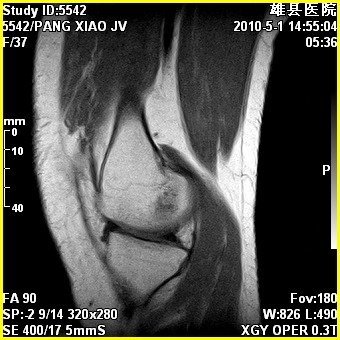

标题: MRI2894:患者右膝关节疼痛两月余,无明显外伤史 [打印本页]

标题: MRI2894:患者右膝关节疼痛两月余,无明显外伤史

右股骨下端前内侧类圆形异常信号,位于干骺端,呈长t1长t2改变,但信号不均,t1图上病灶中心见小片状稍高信号影,t2图上见散在稍低信号影,stir像呈高信号,因病灶较小,缺乏特征性改变,结合患者年龄及部位,考虑嗜酸性肉芽肿可能性大。胫骨关节面下的小囊状异常信号,如果一元论考虑则为嗜酸性肉芽肿,不过发生在这个部位的少见,二元论考虑为邻关节骨囊肿。半月板与前后交叉韧带均未见异常。

右股骨下端前内侧干骺端囊性良性病变,考虑 1内生软骨瘤 2骨囊肿 3肉芽肿。